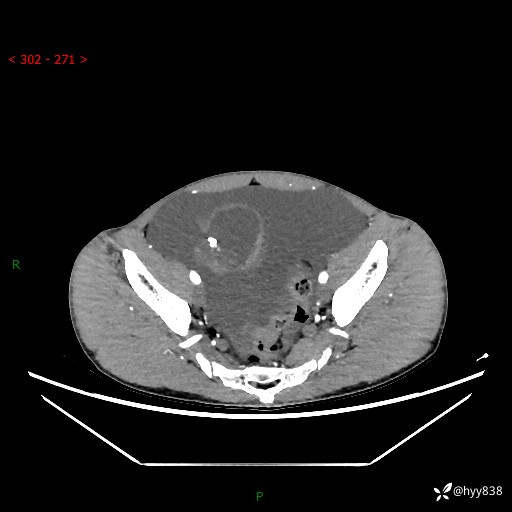

现病史:患者10天前无明显诱因出现腹部胀痛不适,无畏寒发热,无胸痛胸闷,无心慌气短,无恶心呕吐,无腹泻及黑便,无粘液血便及里急后重等症状,4天前在当地县人民医院就诊,行腹部CT示:下腹部占位性病变,腹腔及盆腔积液;今患者为求进一步诊治来我院治疗,门诊以“腹水”收治入院。 发病以来,精神饮食可,大小便正常,体重体力无明显变化。

腹部CT平扫+增强